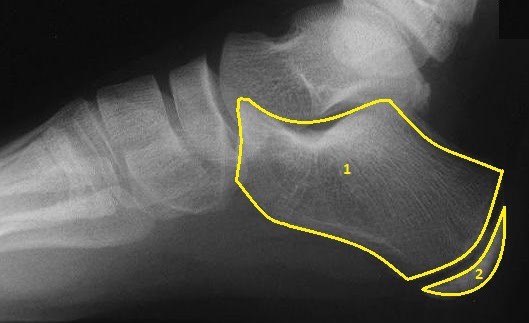

Xray of a Child's Foot

Xray of a Adults Foot